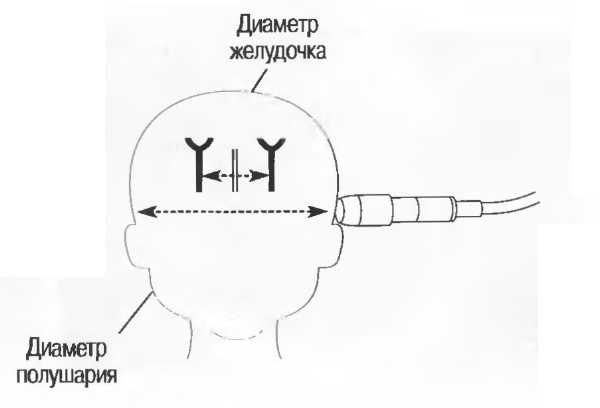

Рис. 13г. Головка плода. Слева: общая чувствительность слишком высока. Справа: общая чувствительность определена правильно, однако она слишком высока для точного измерения бипариетального диаметра.

Рис. 13д. Общая чувствительность слишком низка для исследования внутренней зхоструктуры, но достаточна для точного измерения бипариетального диаметра.

Рис.13е. Слева: плохая визуализация в результате слишком высокого усиления передних отделов; сравните нечеткое изображение передней части головки с достаточно четким изображением задних отделов (сравните рис. 13ги 13д;. Справа: регулировка по глубине была изменена; теперь определяется слишком низкое усиление близких структур и слишком высокое усиление глубокорасположенных структур.